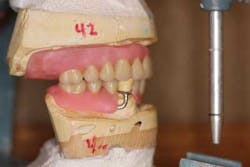

4. Take reliable impressions and bite registrations. The denture/partial is based off what you send to the lab. If the process begins with a poor impression, then you have set yourself up for countless visits with that patient in the chair for adjustments and relines. An excellent final impression material is Acugel/AcuDent by Ivoclar Vivodent. The extended borders on the trays (both for edentulous and dentate impressions) eliminate the need for border molding; furthermore, it is very accurate due to the material’s wettability. Retakes are very few.

6. Don’t skip steps! Verifying the midline, high lip line, vertical dimension, phonetics, and esthetics are essential to achieving a functional and acceptable prosthesis.